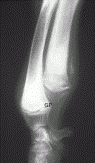

The Musculoskeletal System